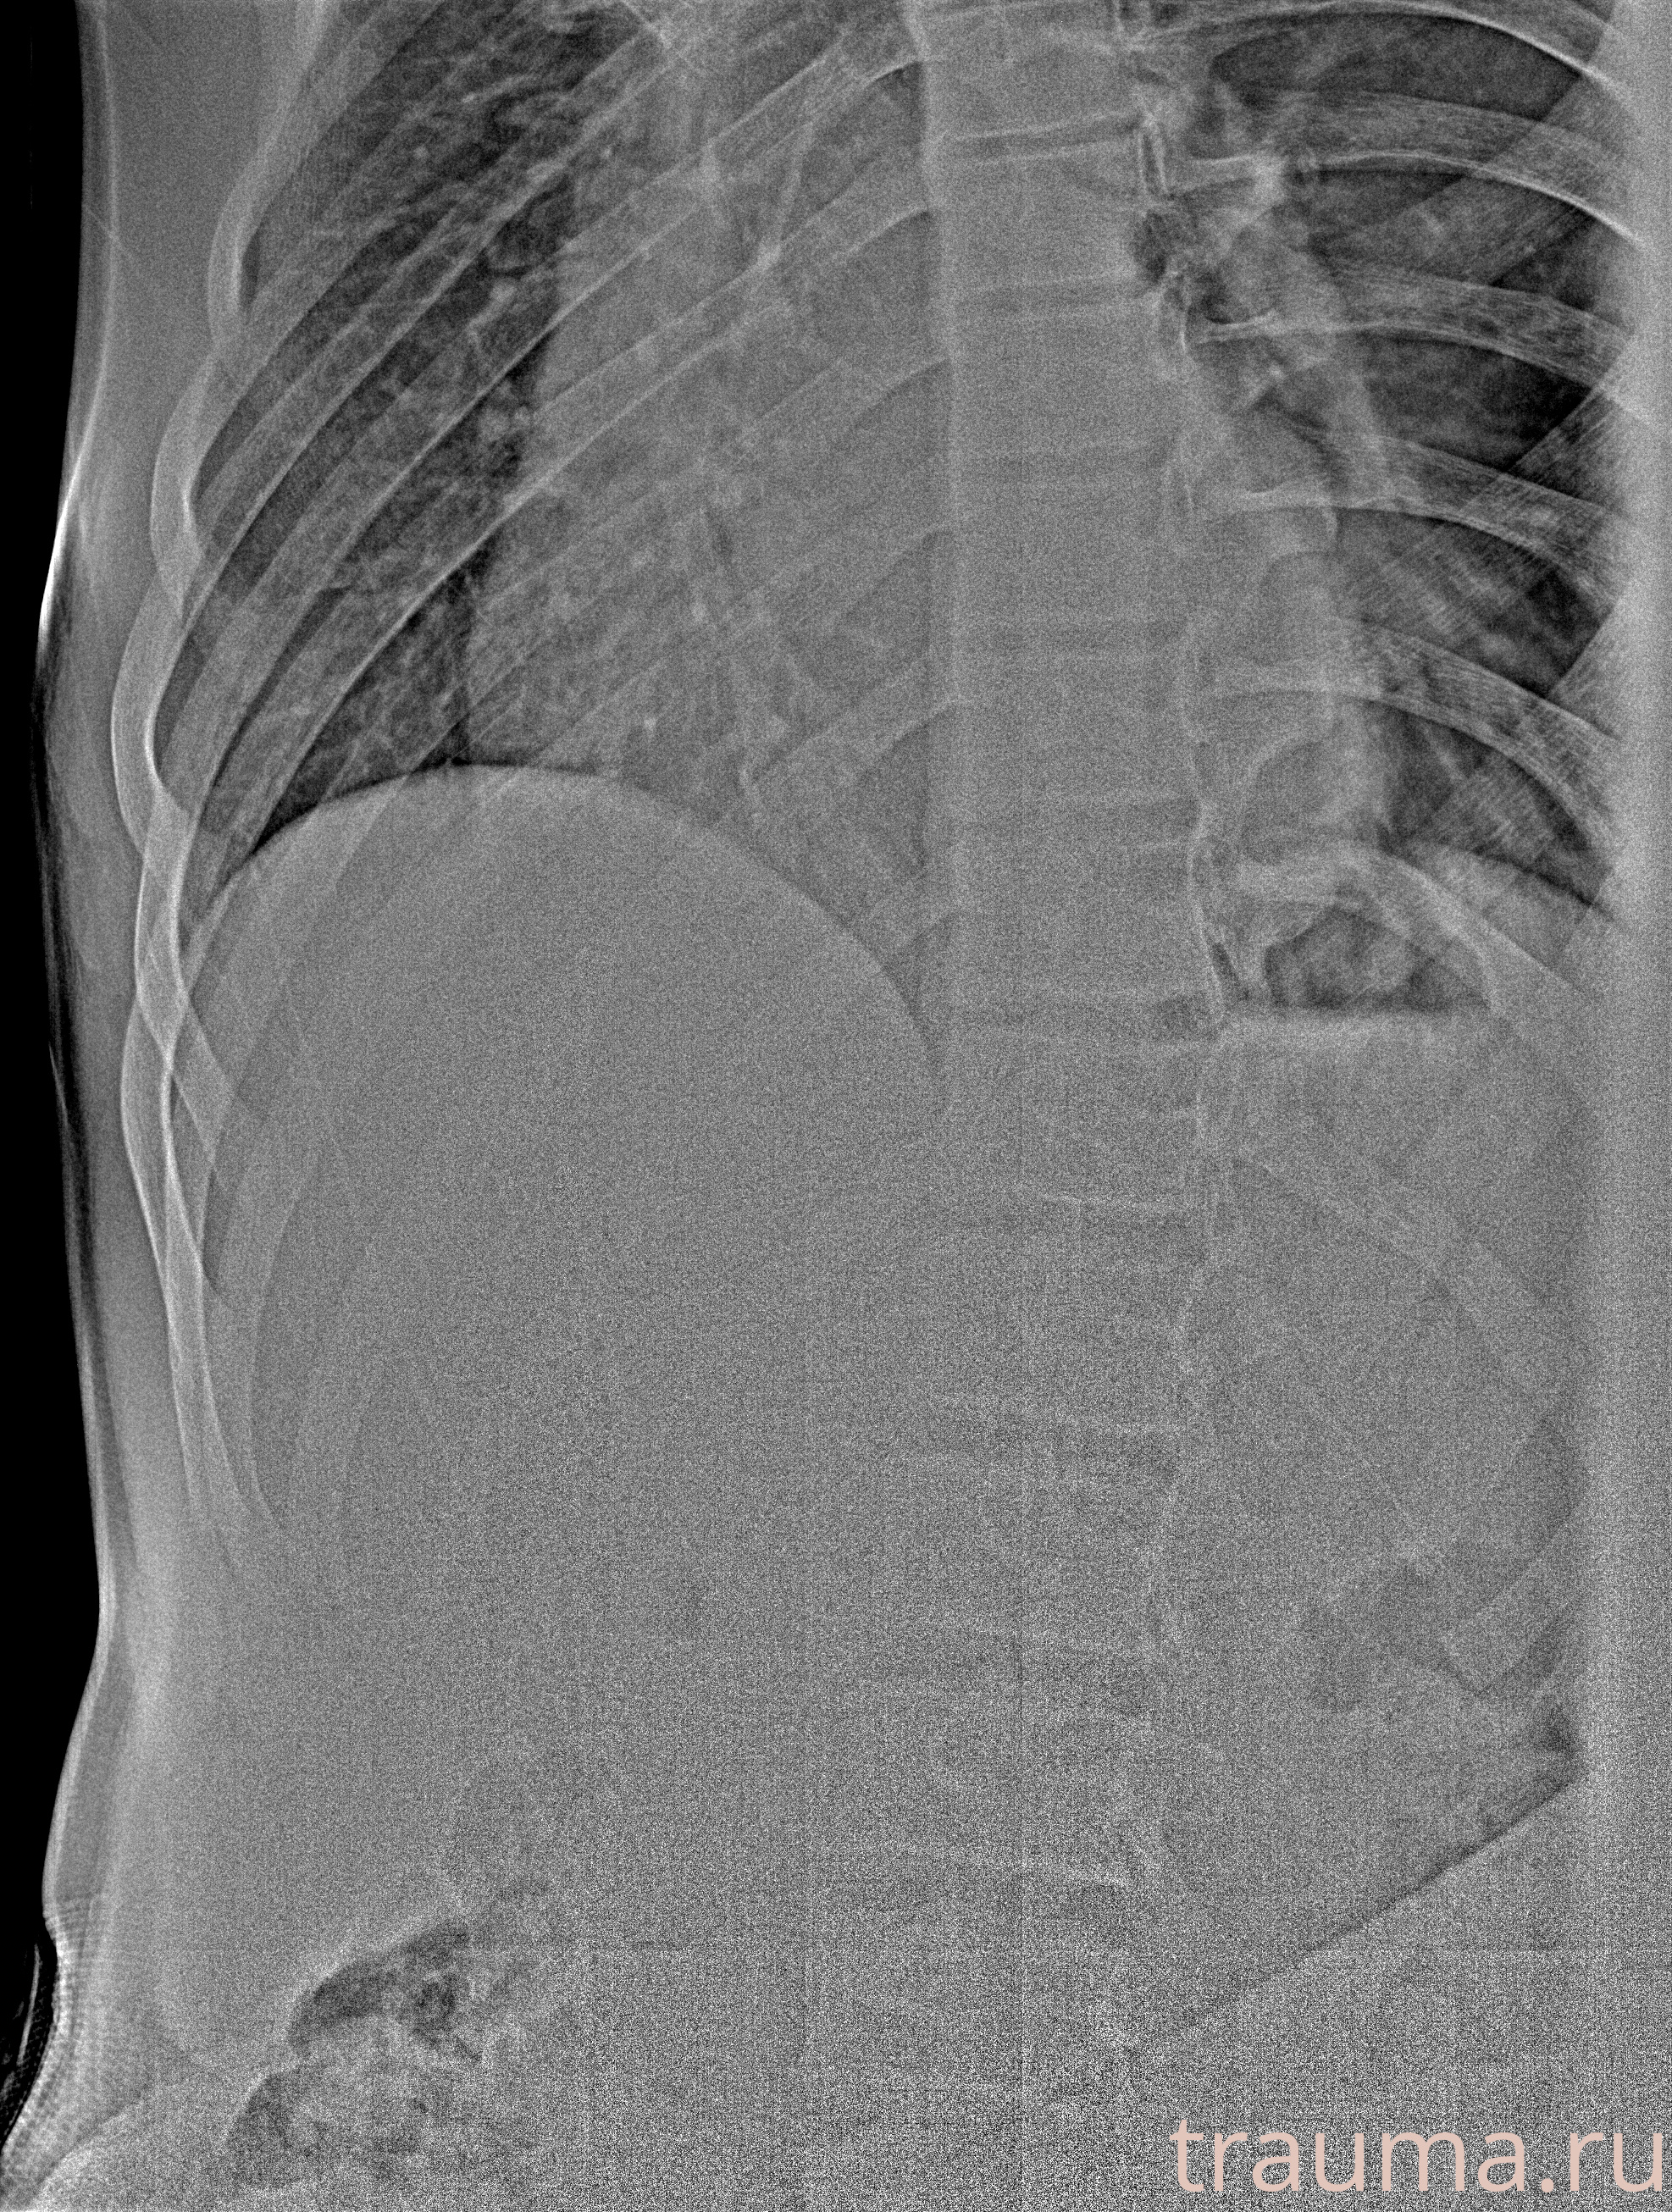

Рентген на дому: по вашему адресу приезжает врач-рентгенолог, травматолог-ортопед с мобильным рентгеновским аппаратом, проводит диагностику травмы или заболевания, делает необходимые рентгенограммы, дает рекомендации по дальнейшему лечению. Получить качественные снимки в домашних условиях возможно благодаря уникальной методике, разработанной МосРентген Центром для института  Склифосовского